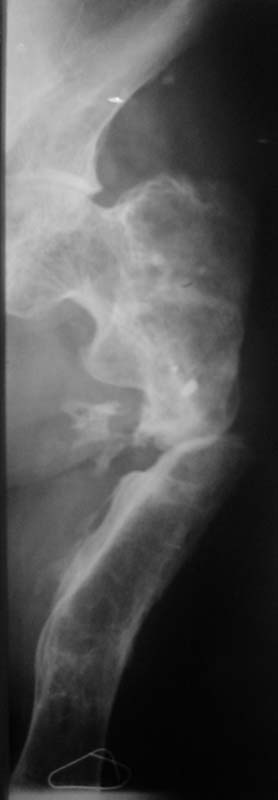

Коллеги! Прошу оказать консультативную помощь! Мужчина, 42 года.В 1994 году - перелом бедра, операция - накостный остеосинтез пластиной.

Осложнение - остеомиелит. Удаление пластины, резекция кости на протяжении 15 см, неудачная попытка замещения дефекта по Илизарову. Сращения не было. В течение 6 лет свищей нет. Укорочение - 13 см. Соматически без особенностей.Лечение? Заранее благодарю! С уважением,А.В.ВладзимирскийДонецкий НИИ травматологии и ортопедииДонецк, Украина

Судя по представленному снимку, есть 3 деформации – Варусная в области ложного сустава - 70°, Вальгусная - 35° в средней трети бедра, и ещё одна вальгусная 8° в области дистального метаэпифиза бедренной кости. Если бы пациент попал ко мне, я сделал бы трилокальный остеосинтез – Открытый погружной копрессионный в области ложного сустава, остеотоми на вершине деформации средней трети бедра для удлинения и коррекции деформации и коррегирующую остеотомию через верхний край мыщелков бедренной кости. Для оппонентов такой тактики сразу оговорюсь, что коррекция анатомической и механической оси при наличии срастающегося ложного сустава критична для профилактики рефрактуры.

Просится "русский замок" с последующим удлинением на двух уровнях. Нельзя ли посмотреть тазобедренный сустав?